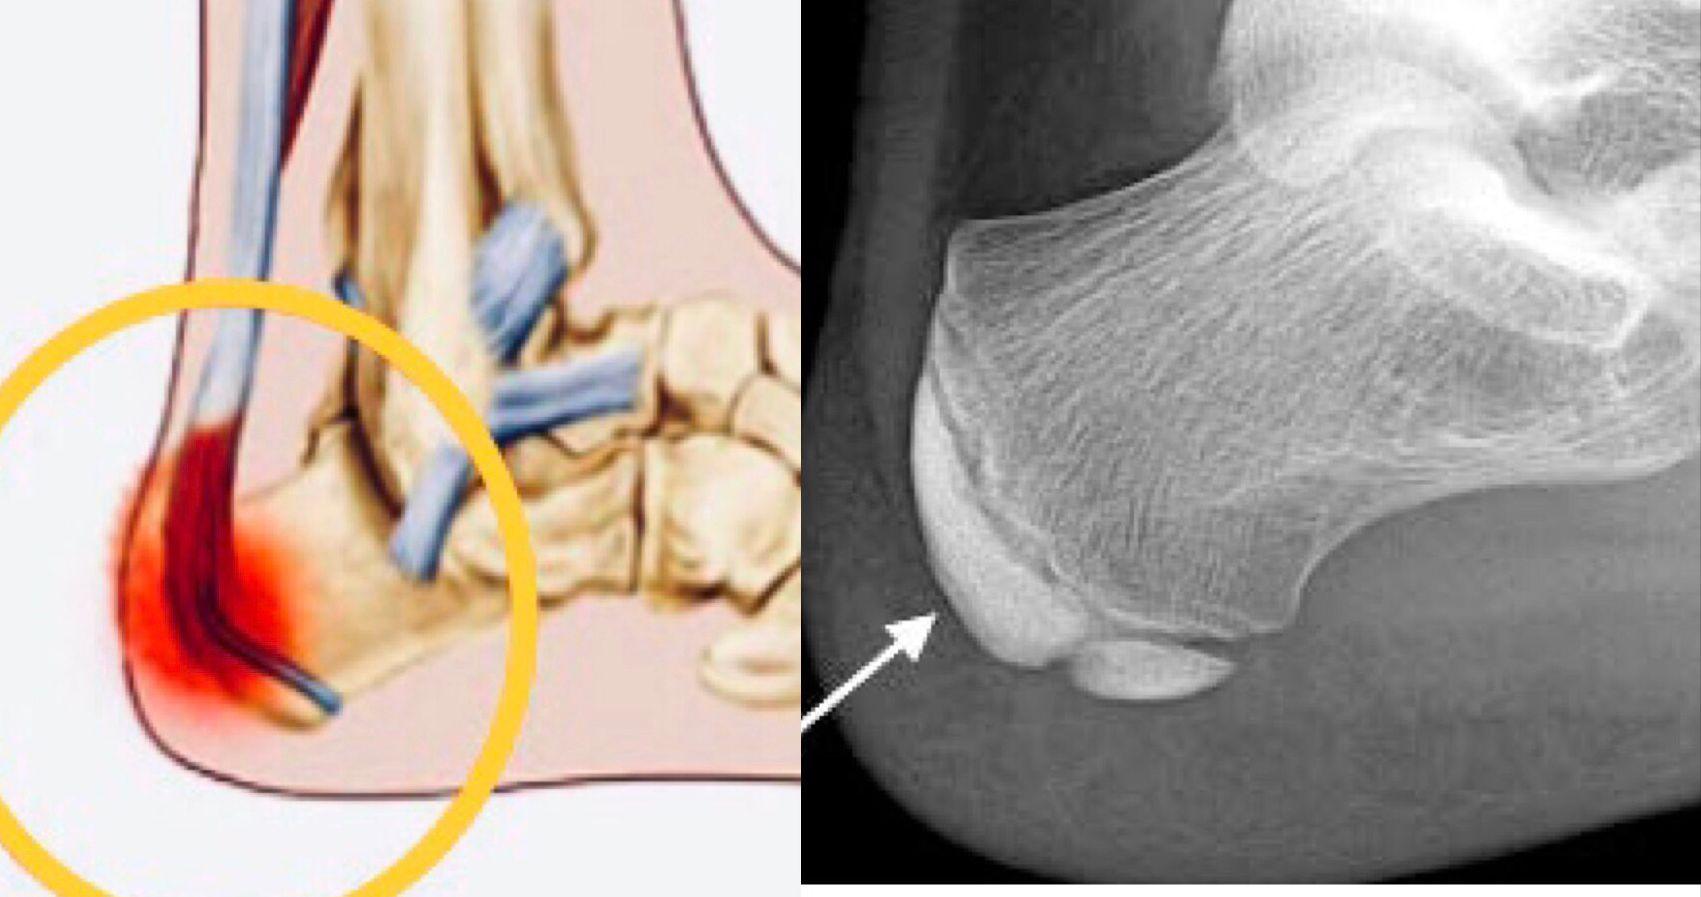

跟骨骨骺炎(Severs disease),是一種源自跟骨生長板的炎症。此生長板位於跟腱(阿基里斯腱)連接跟骨的位置,是賴以成長的軟骨組織。跟骨炎是學童階段裡最常見的跟骨痛症,病發年齡介乎815歲。當跟骨生長板仍未閉合,學童卻在課外活動裡爭取加入校隊;在過度的運動操練下,尤其是需要跑和跳的運動(例如是田徑、球類或跳舞等),便會使跟腱經常拉扯生長板,從而產生炎症。

兒童患者通常會在運動後,感到腳跟單側或雙側疼痛。痛楚或會促使他們用腳尖行路,以減少跟骨與地面接觸。除了跟部有壓痛外,臨床檢查或會發現跟腱和小腿肌肉過緊,使生長板承受額外張力。至於X光檢查,可排除其他痛症成因,包括運動操練引致的應力性骨折,和細菌感染引發的跟骨骨髓炎。然而X光下尚未閉合的生長板,或會有家長誤以為是骨折裂痕,將跟骨分為「大跟骨」和「細跟骨」(骨骺),正如坐落在九龍塘的名幼般設有分部校舍。